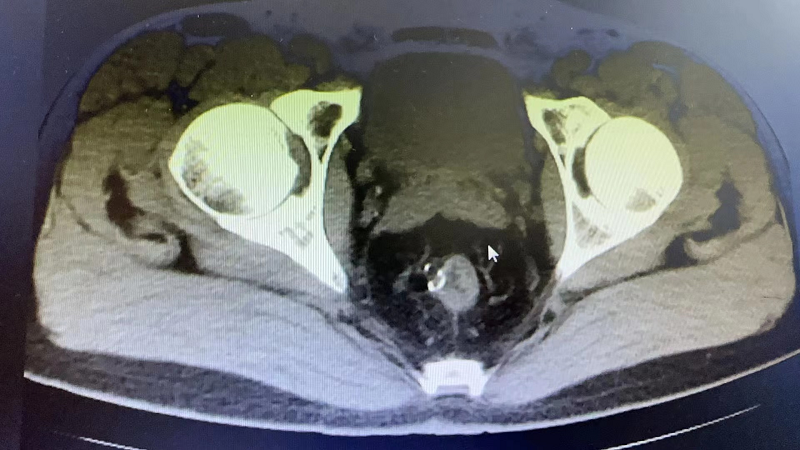

近期,73岁的J大爷比较烦恼,他出现了排尿困难、疼痛症状,这严重影响了J大爷的生活。在家人的陪伴下,J大爷辗转当地多家医院,但都因为J大爷有多种基础疾病未能如愿,最终在亲戚的介绍下来到我院泌尿外科就诊。通过接诊医生的详细询问病史并结合相关检查,诊断J大爷为:膀胱结石、泌尿道感染,建议J大爷住院行微创手术治疗。

经询问和检查,J大爷有重度贫血、慢阻肺、呼吸衰竭、冠心病支架植入术后等既往病史,泌尿外科高茂主任特邀多个专科主任前来参加会诊,各位专家积极发言,围绕J大爷的基础疾病、手术风险等展开讨论,最后确定适合J大爷的诊治方案。

手术由泌尿外科高茂主任亲自操刀,在麻醉科、手术室的倾力配合下,一小时就为J大爷完成尿道内镜下膀胱结石钬激光碎石术,成功解决了约3.0*2.0cm的大结石。